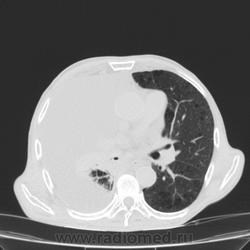

Пожилой мужчина, лечился по н/д правостороннней пневмонии в терап/отделении. Жалобы на одышку, кашель. По результатам Р-контроля после лечения направлен на КТ легких с диагнозом: плеврит справа, распад? В корне правого легкого вижу объёмное образование, с распадом. Смущают размеры плеврита,очень много жидкости, почти до 3 ребра. Анализы крови спокойные- L4,0-6,6, СОЭ 12-16мм. Неужто ТБС, отсев бы был при таком огромном поражении. В посеве мокроты-100% высев клебсиэллы пневмоние. Мокрота на общий анализ в работе-собирает с трудом, изза отсутствия мокроты. Плевральную пункцию еще не проводили. Н азначила бронхоскопию и плеврал пункцию. Как думаете, уважаемые коллеги, это онкопроцесс или тбс распад?

По-моему там и слева лимфаденопатия корня легкого, гидроторакс туберкулезной этиологии редко у пожилых бывает

Небольшое количество увеличенных лимфоузлов, и те - не сказать, чтоб были очень крупными. От эмпиемы до онкологии... Умеренное количество жидкости в перикарде, толщиной слоя до 13-14 мм. При подобной картине не вижу смысла гадать по сжатому лёгкому, пишу так: массивный выпот справа, около 2500 мл, диафрагма оттеснена жидкостью каудально, печень (!!!) смещена каудально и вправо. Легкое справа значительно компрессировано жидкостью, оценка проходимости бронхов и состояния легочной паренхимы (кроме имеющейся эмфиземы) практически невозможна. Необходима пункция плевральной полости справа (цитология, ВК, посев на микрофлору и проч), КТ-контроль после эвакуации жидкости.